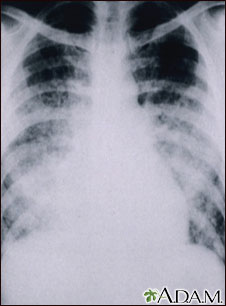

Chickenpox, acute pneumonia - chest X-ray

This chest X-ray shows cloudiness throughout the lungs, caused by acute pneumonia due to chickenpox. Pneumonia, as a complication of chickenpox, rarely occurs in children, but occurs in about one-fifth of adults with chickenpox.